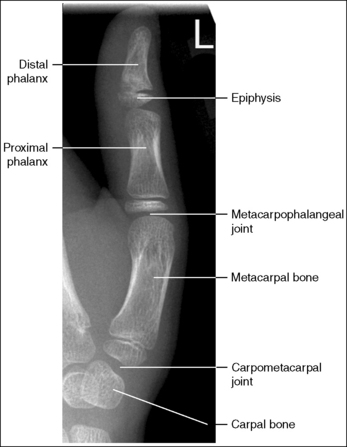

See Figure 4-10 and Box 4-4.

The digit of interest is in a lateral projection. The anterior aspect of the middle and proximal phalanges demonstrates midshaft concavity, and the posterior aspects of the phalanges show slight convexity.

• A lateral finger projection is accomplished by rotating the affected finger 90 degrees from the PA projection (Figure 4-11). Whether the hand is rotated internally or externally to obtain this goal depends on which direction will bring the finger closer to the IR. Typically, when the second and third fingers are imaged, the hand is rotated internally and, when the fourth and fifth fingers are imaged, the hand is rotated externally.

• Distinguishing lateral projection from rotated projection. To understand the difference between a truly lateral digit projection and a lateral projection that is rotated, study a finger skeleton in lateral and PA and AP oblique projections. Note how the midshaft concavity of the middle and proximal phalanges varies as the digit is rotated. In a lateral projection, the anterior aspect of these phalanges is concave, but the posterior aspect demonstrates slight convexity. In PA and AP oblique projections, both sides of the middle and proximal phalangeal midshafts demonstrate concavity, but the side toward which the anterior surface is rotated demonstrates a greater degree of concavity than the side toward which the posterior surface is rotated. The soft tissue width at either side of the phalanx also changes in the lateral and PA and AP oblique projections. More soft tissue is present on the side of the phalanges toward which the anterior surface is rotated (see Image 7).

The IP joints are visible as open spaces, and the phalanges are not foreshortened.

• The IP joints are open, and the phalanges are demonstrated without foreshortening as long as the finger was positioned parallel with the IR and the central ray was perpendicular to and centered with the PIP joint.

• When the third and fourth digits are imaged, they are positioned at a greater OID than the second and fifth digits. To keep the third and fourth digits parallel with the IR, it may be necessary to place an immobilization device beneath their distal phalanges. When a finger is not positioned parallel with the IR and perpendicular to the central ray, the IP joint spaces are closed and the phalanges are foreshortened.

The PIP joint is at the center of the exposure field. The distal, middle, and proximal phalanges and the metacarpal head of the affected digit are included within the collimated field.

• Center a perpendicular central ray to the PIP joint to place it in the center of the image. Open the longitudinal collimation to include the distal phalanx and the metacarpal head. Transversely collimate to within 0.5 inch (1.25 cm) of the finger skin line.